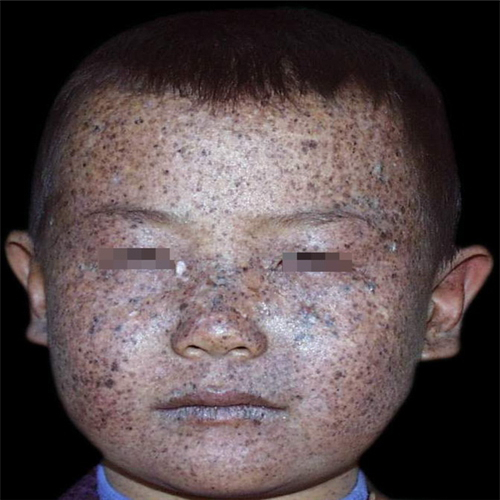

面部皮脂腺痣

面頸部皮脂腺痣

老人面部皮脂腺痣